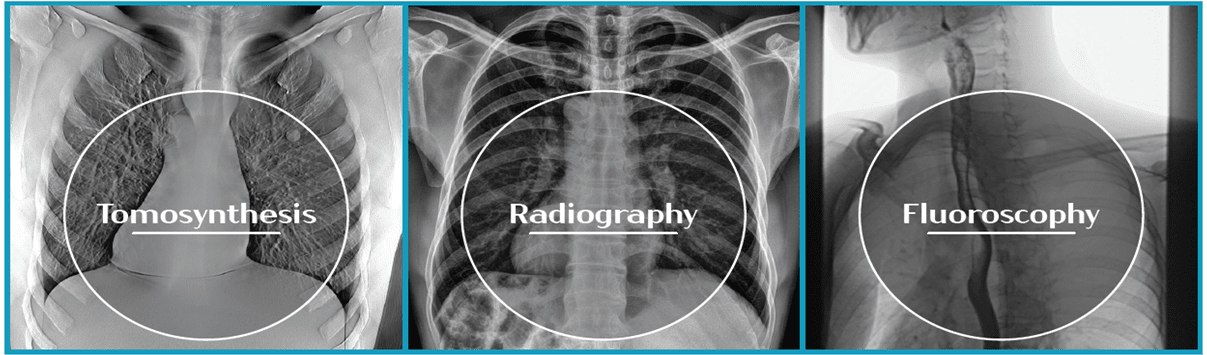

X-ray imaging method based on the reconstruction of sequential

images (tomograms) with a fixed distance between slices

StriXion 전용 소프트웨어는 사용자 편의성을 반영한 최신 트렌드의 직관적인 인터페이스를 통해

실시간 투시 영상, 일반 엑스레이 영상, 단층 영상을 제공합니다.

자체개발 소프트웨어를 통해 유일하게 사용할 수 있는 특수 기능을 포함하며,

사전 조치를 위한 자가진단 기능과 효율적인 업무를 위한 도구 툴을 제공합니다.

StriXion 전용 소프트웨어는 각 모드별 영상처리 기술을 통해 진단에 유용한 고품질 영상을 제공하여 효과적인 업무가 가능하며,

전문적인 영상 촬영을 위한 디지털 가이드 제공으로 사용자의 업무 만족도를 향상시켜 드립니다